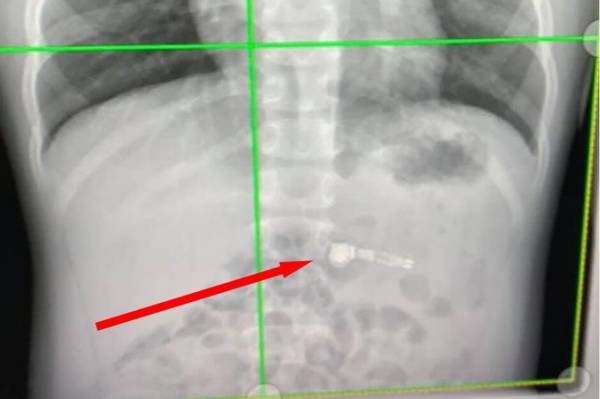

The X-ray image clearly showed that there was an Airpods earbud just below the rib cage. He was holding the stem of the earphone when he swallowed it.

In a Facebook post, the boy’s mother, Kiara Stroud, shared an X-ray image that belongs to her son. The image clearly showed that there was a wireless earbud just below the rib cage. He was holding the stem of the earphone when he swallowed it.

Since the earphone had metal in it, it showed up in the X-ray image. The boy was admitted to an emergency room at the Children’s Healthcare of Atlanta. The doctors said that the Airpod will come out on its own. With this incident, parents really need to rethink if they ever want to get their 7-year-old kids a pair of Apple AirPods.